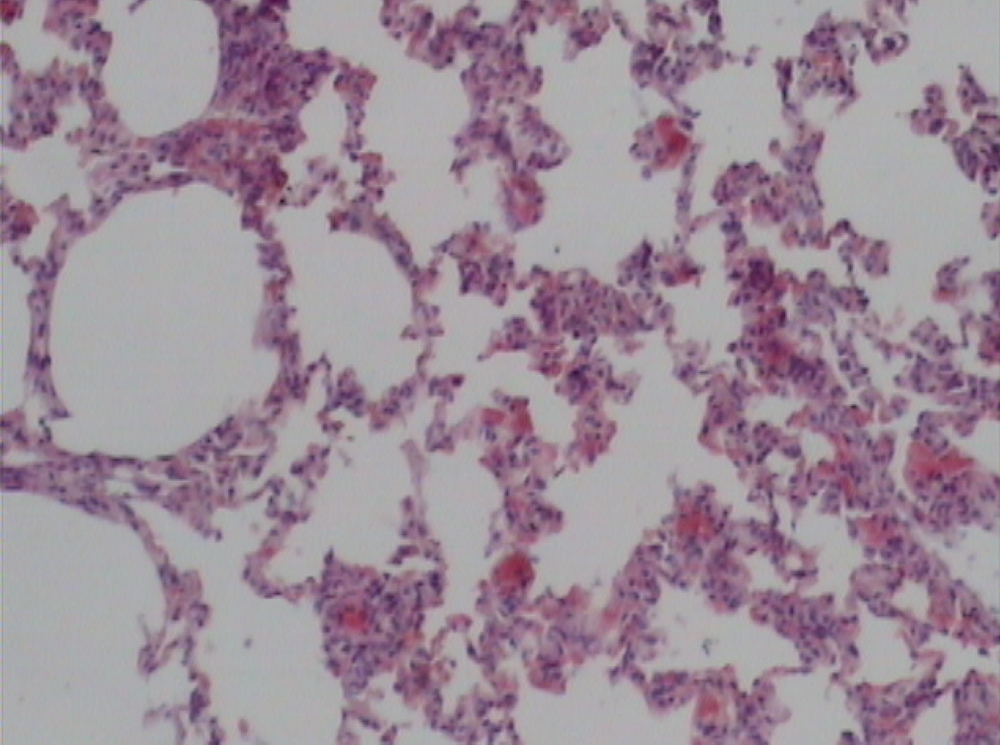

Supplementation of probiotics will effectively prevent neutrophil infiltration of the lung and also reduce the subsequent tissue destruction, as demonstrated in studies with inflammation induced by cecal ligation and puncture (CLP). A synbiotic formulation, Synbiotic 2000 Forte (see further below), was administered orally before the induced trauma and effectively prevented both neutrophil accumulation and tissue destruction in the lungs [50]. Most interestingly, these effects were obtained also when the LAB of the composition were injected subcutaneously (Figure 1,Figure 2,Figure 3) [51].

The average neutrophil count in the lungs (average of five fields) was: mixture of LAB and bioactive fibers 9.00 ± 0.44 (1), only LAB 8.40 ± 0.42 (2), only bioactive fibers 31.20 ± 0.98 (3), placebo (non-fermentable fiber) 51.10 ± 0.70 (4). The reduction of inflammation by the treatment was also demonstrated by significant reductions in myeloperoxidase (MPO), malondialdehyde (MDA), and nitric oxide (NO): MPO being 25.62 ± 2.19 (1), 26.75 ± 2.61 (2), 56.59 ± 1.73 (3), and 145.53 ± 7.53 (4) respectively (resp.), MDA 0.22 ± 1.31 (1), 0.28 ± 3.55 (2), 0.48 ± 5.32 (3) and 0.67 ± 2.94 (4) resp. and NO 17.16 ± 2.03 (1), 18.91 ± 2.24 (2), 47.71 ± 3.20 (3) and 66.22 ± 5.92 (4) resp.—all differences being statistically significant (>0.05).

Figure 3.

Prebiotic group.